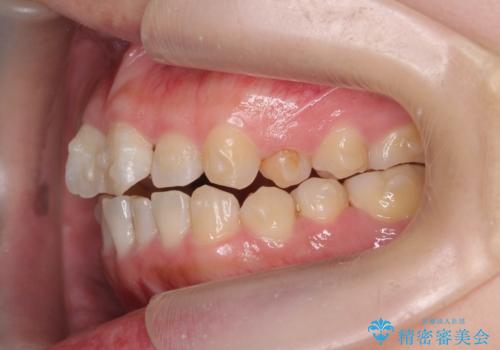

前歯のねじれをマウスピース矯正インビザラインで治療

- 長年気になっている、前歯のねじれの矯正治療を希望され来院されました。

十分にマウスピース矯正インビザラインで治療が可能と判断し、治療を進めることとしました。

長年気になっていた前歯のねじれが、ワイヤーをつけることなく矯正を行うことができ、大変喜んでいただくことができました。